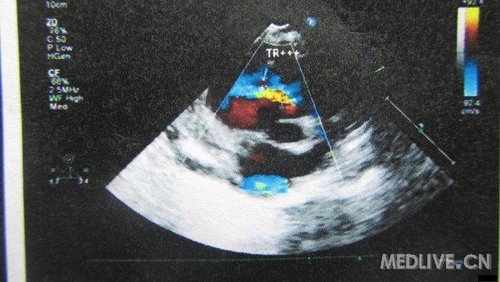

患儿,女,6月,足月剖腹产,出生后家长发现喘憋,未重视。现症状加重,不能喂食而就诊!

片子列出,急盼高手指点,不知生存几率有几分?